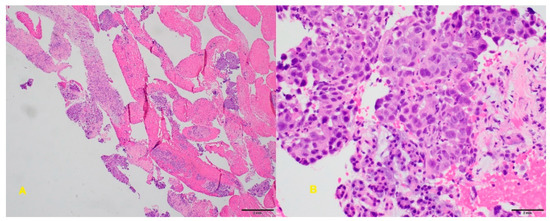

6.4. Endoscopic Ultrasound-Guided Fine-Needle Biopsy

- Ayres, L.R.; Kmiotek, E.K.; Lam, E.; Telford, J.J. A comparison of endoscopic ultrasound-guided fine-needle aspiration and fine-needle biopsy in the diagnosis of solid pancreatic lesions. Can. J. Gastroenterol. Hepatol. 2018, 2018, 1–6. [Google Scholar] [CrossRef]

- Van Riet, P.A.; Larghi, A.; Attili, F.; Rindi, G.; Nguyen, N.Q.; Ruszkiewicz, A.; Kitano, M.; Chikugo, T.; Aslanian, H.; Farrell, J. A multicenter randomized trial comparing a 25-gauge EUS fine-needle aspiration device with a 20-gauge EUS fine-needle biopsy device. Gastrointest. Endosc. 2019, 89, 329–339. [Google Scholar] [CrossRef]

- Asokkumar, R.; Ka, C.Y.; Loh, T.; Ling, L.K.; San, T.G.; Ying, H.; Tan, D.; Khor, C.; Lim, T.; Soetikno, R. Comparison of tissue and molecular yield between fine-needle biopsy (FNB) and fine-needle aspiration (FNA): A randomized study. Endosc. Int. Open 2019, 7, E955–E963. [Google Scholar] [CrossRef]

- Facciorusso, A.; Bajwa, H.S.; Menon, K.; Buccino, V.R.; Muscatiello, N. Comparison between 22G aspiration and 22G biopsy needles for EUS-guided sampling of pancreatic lesions: A meta-analysis. Endosc Ultrasound. 2019, 10. [Google Scholar] [CrossRef]

- Khan, M.A.; Grimm, I.S.; Ali, B.; Nollan, R.; Tombazzi, C.; Ismail, M.K.; Baron, T.H. A meta-analysis of endoscopic ultrasound–fine-needle aspiration compared to endoscopic ultrasound–fine-needle biopsy: Diagnostic yield and the value of onsite cytopathological assessment. Endosc. Int. Open 2017, 5, E363–E375. [Google Scholar] [CrossRef]